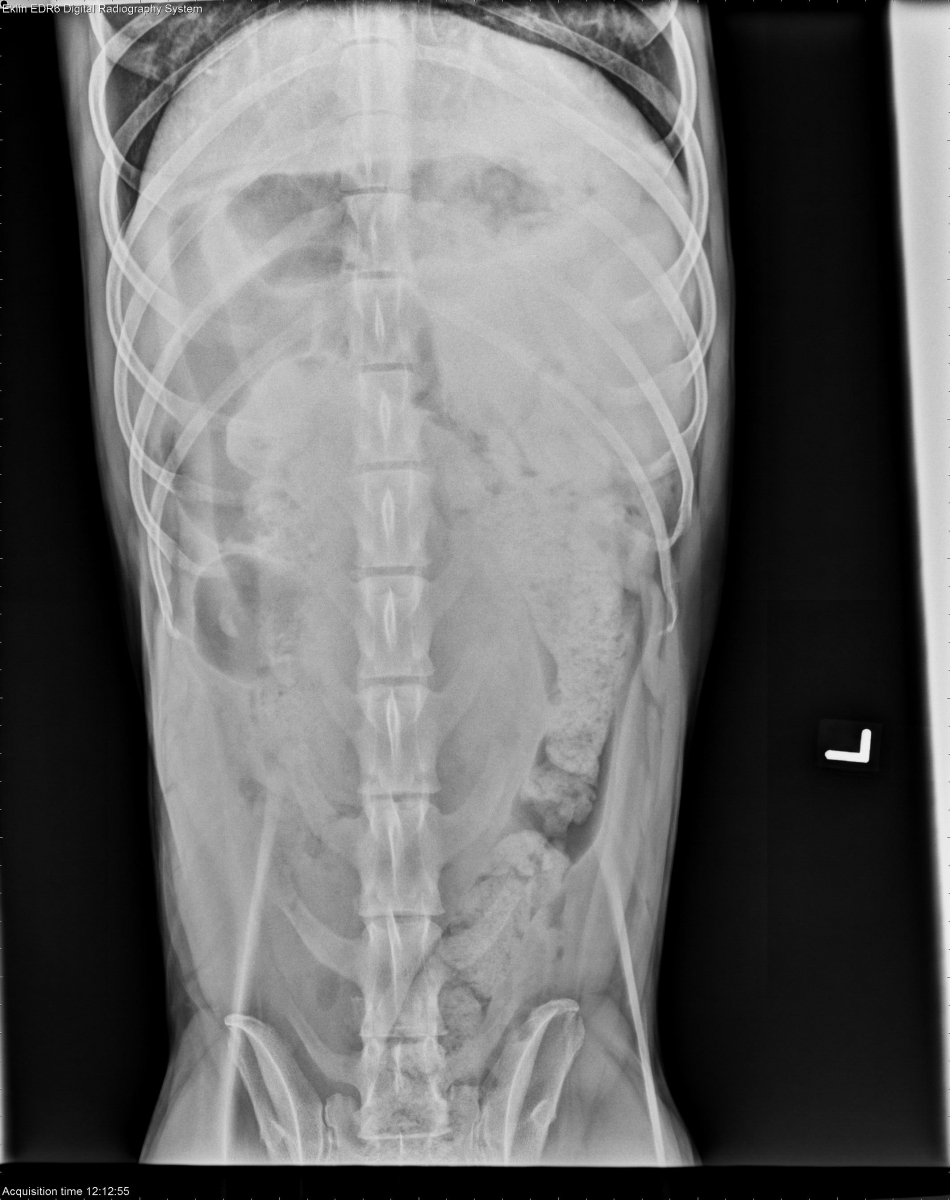

Today’s case is a 4 year old female neutered Greyhound with acute fever, tachycardia, and vomiting. What are the critical findings?

VD Abdomen

There is poor peritoneal detail in the abdomen, with regions of gas opacity that are not apparently contained within the gastrointestinal tract. The duodenum is distended on multiple projections. The remainder of the abdominal organs are normal.

Peritoneal fluid and free gas are consistent with septic peritonitis, possibly due to bowel rupture. Distended duodenum may be due to entertitis or obstruction.

Abdominal ultrasound was performed, revealing free gas, free fluid, and a jejunal mass with gas tracking through the wall to the serosal surface. Euthanasia was elected, and T-cell lymphoma with multiple sites of rupture was diagnosed on necropsy.